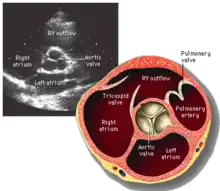

La válvula aórtica normalmente tiene tres valvas o cúspides de forma semilunar.[Nota 1] Suelen llamarse cúspide coronaria izquierda, cúspide coronaria derecha y cúspide no coronaria.[Nota 2] Cada valva está separada de la vecina por una comisura.[2][3][4][5]

La válvula aórtica está situada detrás de la válvula pulmonar, en la enfermedad congénita llamada transposición de los grandes vasos, la situación de estas dos válvulas se invierten, la válvula anterior es la válvula aórtica.